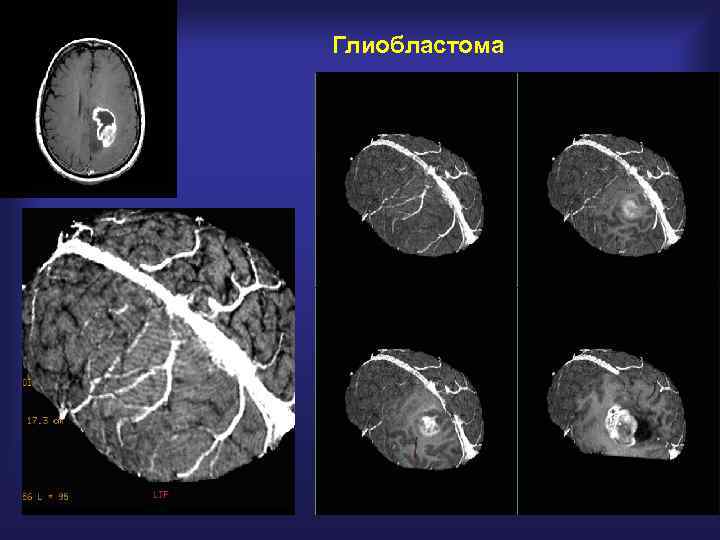

Глиобластома